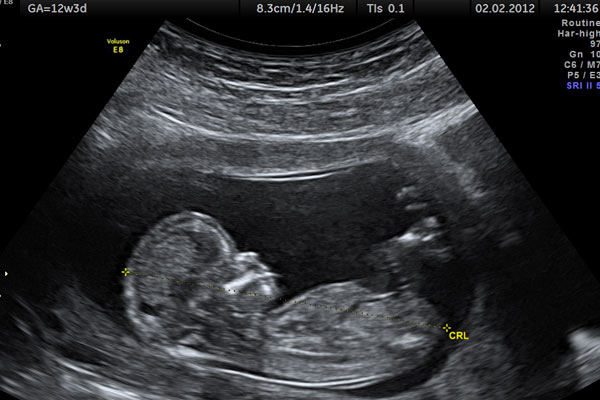

فوق تخصص زنان و زایمان با اشاره به اینکه مناسبترین زمان برای انجام سونوگرافی غربالگری ۱۲ هفتگی جنین است، گفت: مادرانی که سابقه ژنتیکی ناهنجاریهای کروموزومی دارند باید نسبت به سونوگرافی غربالگری اقدام کنند.

عضو هیأت علمی دانشگاه علوم پزشکی تهران عنوان کرد: بهترین زمان انجام سونوگرافی و آزمایش غربالگری جنین 11 تا 13 هفته و 6 روز بوده و در واقع در 12 هفتگی مناسبتترین زمان برای انجام این عمل است.